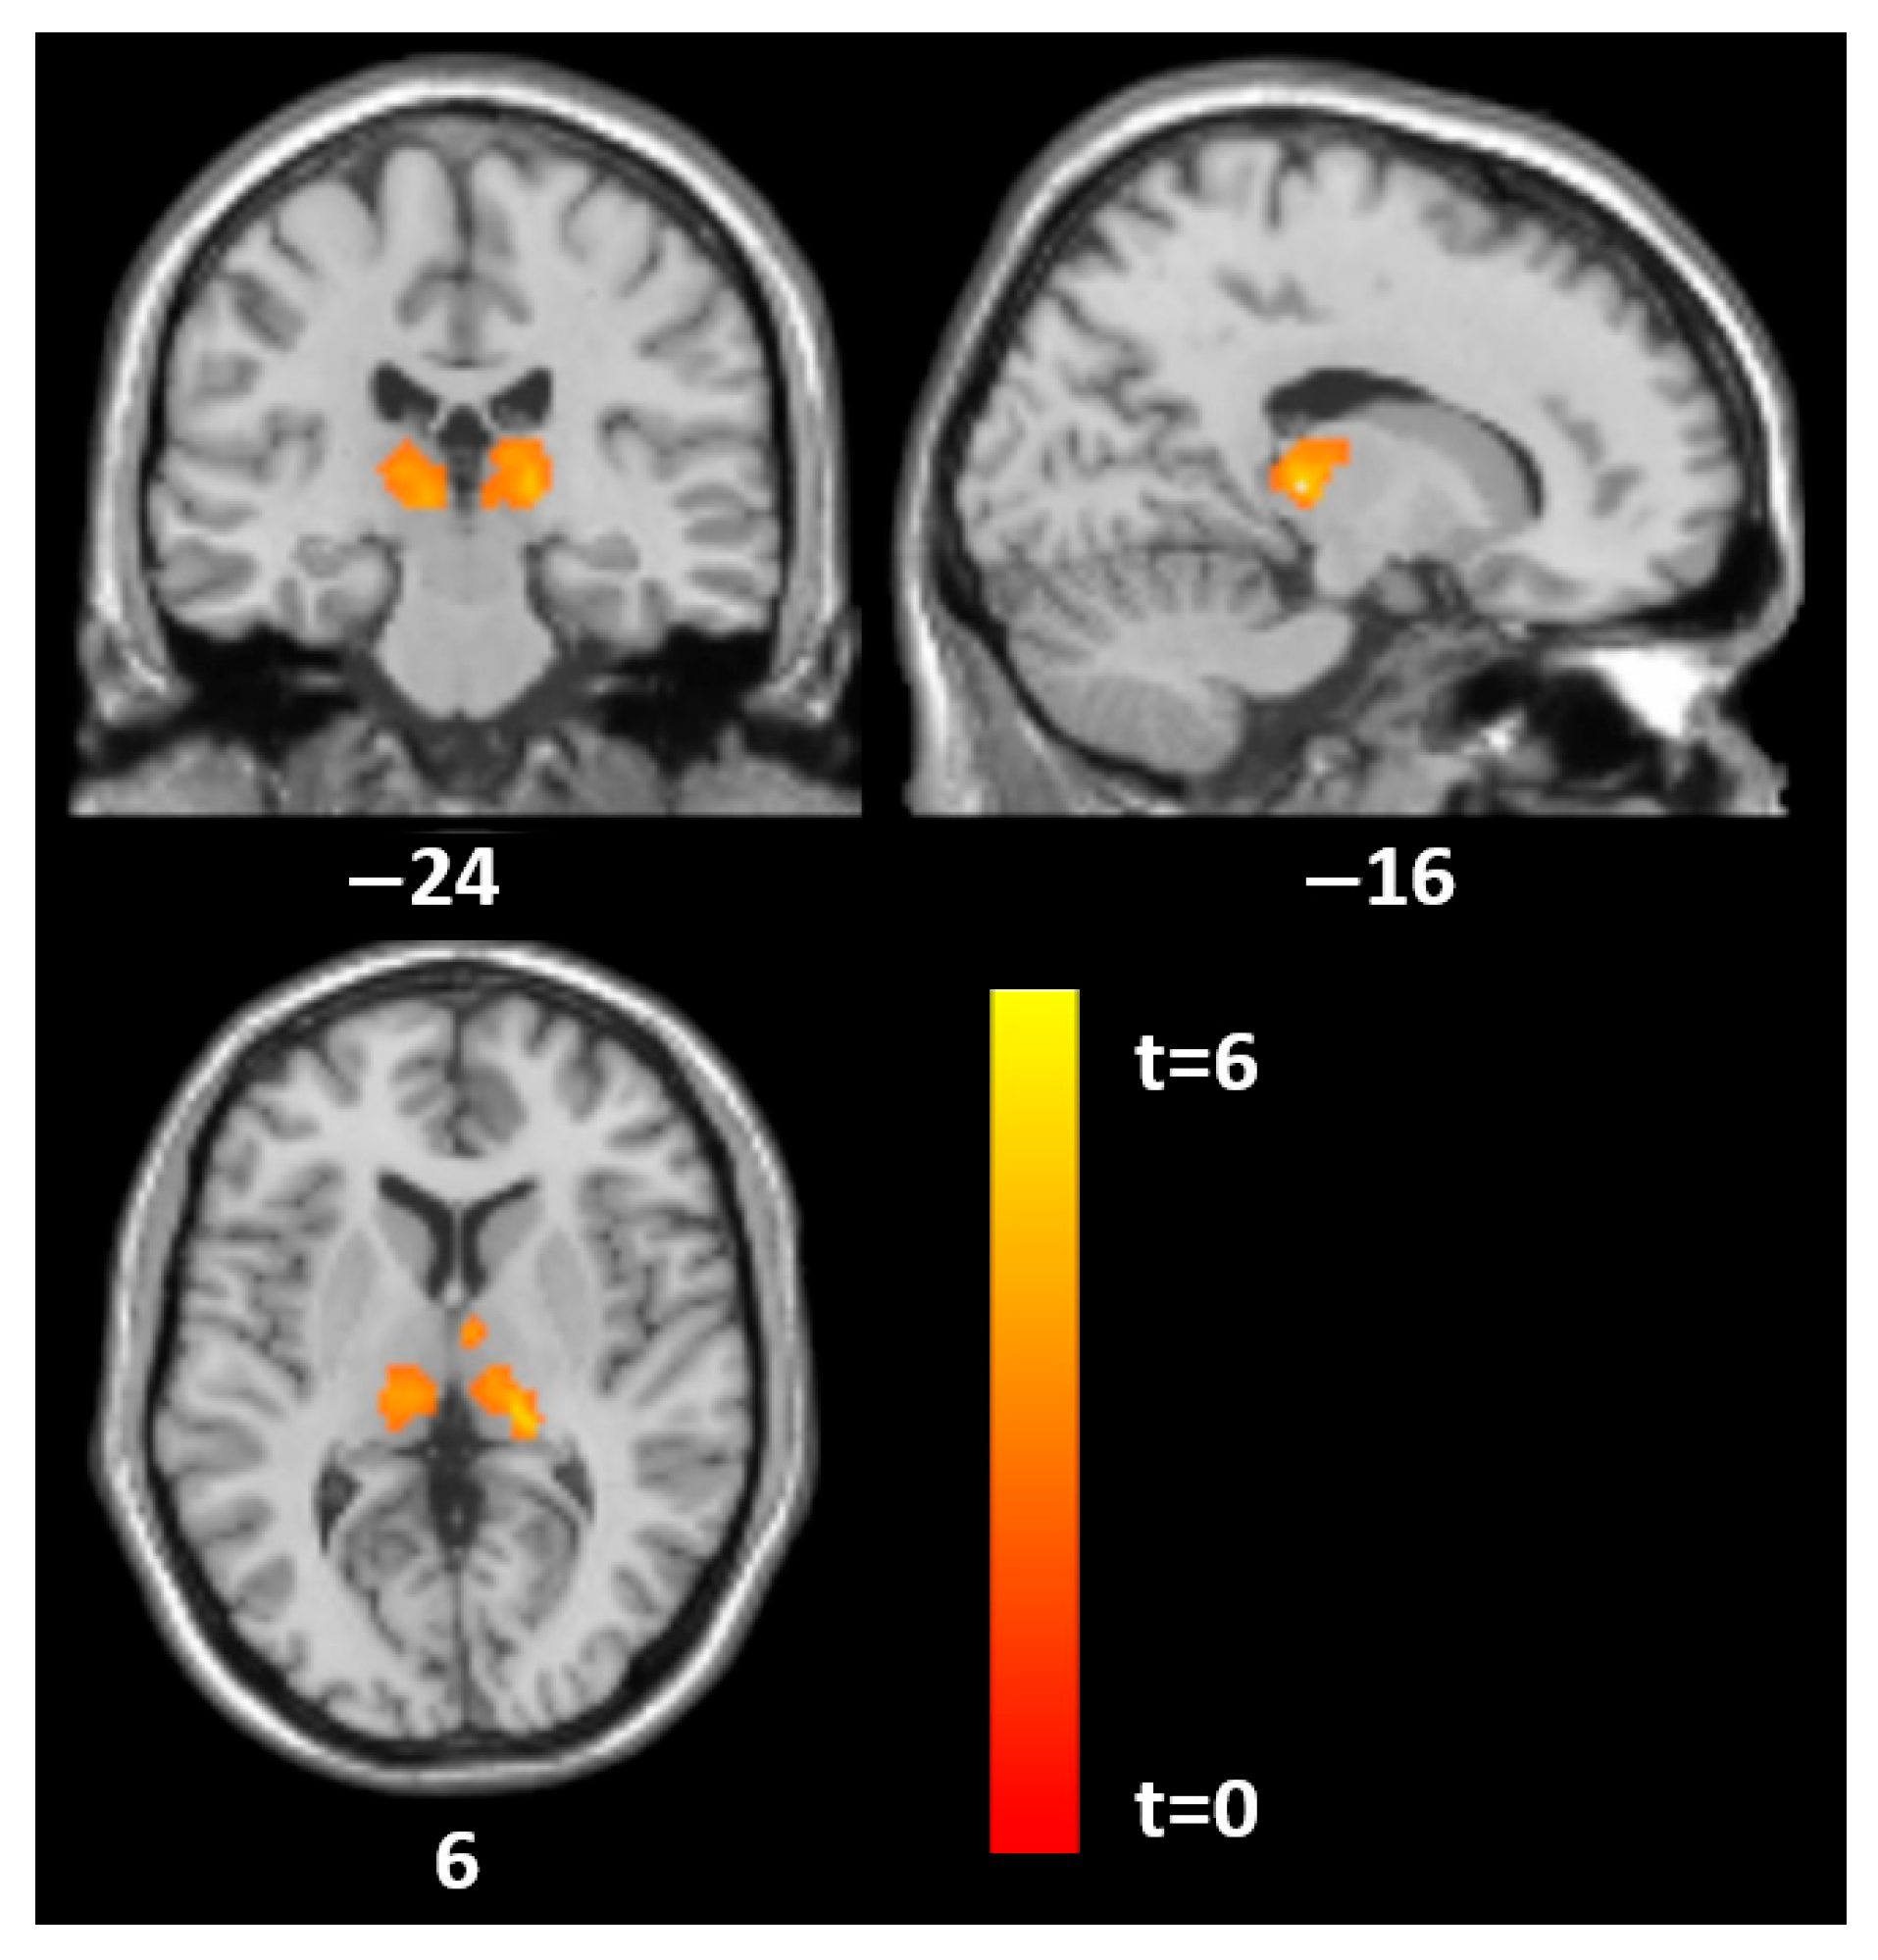

| Histrionic | |||||||

| Thalamus | 845 | −17 | −26 | 5 | 6.5 | 0.002 | 0.01 |

| 666 | 15 | −20 | 9 | 4.7 | 0.009 | ||

| Left superior parieto-occipital | 905 | −30 | −66 | 54 | 5.9 | 0.001 | |

| Borderline | |||||||

| Thalamus | 1149 | 0 | −21 | 9 | 4.8 | <0.001 | 0.01 |

| −5 | −11 | 12 | 4.3 | ||||